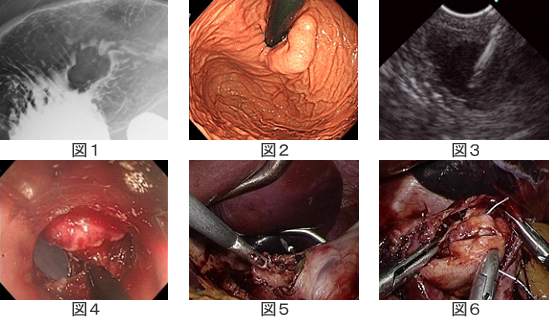

胃粘膜の下にできる腫瘍(胃粘膜下腫瘍)は良性から悪性のものがあります。最も多いのは消化管間質腫瘍(Gastrointestinal stromal tumor: GIST)で悪性腫瘍です。当院では超音波内視鏡下穿刺生検と呼ばれる内視鏡を用いた針生検で診断を行った後に治療を行っています。

現在、一般に行われている手術は腹腔鏡下胃局所(部分)切除ですが、腹腔鏡で胃の外側から観察すると同時に、胃内視鏡で胃の中から腫瘍を観察することによって最小限の切除が可能となります。それによって胃の変形が少なくなり胃の機能温存が可能となります。当院では熟練した外科医と内視鏡医によるこの合同手術(LECS)を積極的に行っています。

LECSの一例

図1,2 胃の入り口に近い腫瘍でありLECSでなければ術後に胃の狭窄を起こす可能性があります。

図3 超音波内視鏡を用いた針生検。

図4 胃内腔からの切開。

図5, 6 腹腔鏡の画面